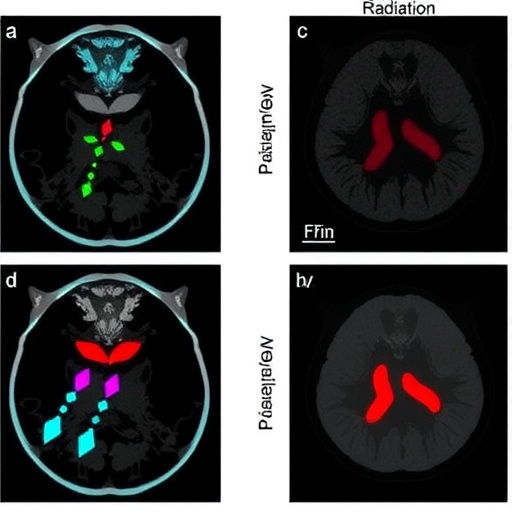

The current study employed pharmacological agents to disrupt the neddylation cascade in models of PAX3–FOXO1 rhabdomyosarcoma, revealing an accumulation of DNA double-strand breaks (DSBs). These breaks represent the most lethal form of DNA damage, challenging the integrity of the cancer genome and precipitating cellular demise. Intriguingly, the induction of DSBs in these tumors was accompanied by a marked deceleration in tumor growth when studied in vivo, underscoring the potential clinical relevance of neddylation inhibition.

Moreover, the researchers uncovered a significant enhancement in the tumor cells’ sensitivity to ionizing radiation following neddylation blockade. Radiosensitivity is a crucial factor in cancer treatment, and many tumors, including PAX3–FOXO1 rhabdomyosarcoma, display inherent or acquired resistance to radiation therapy. By promoting radiosensitivity, neddylation inhibitors could synergize with existing radiotherapy regimens, amplifying their efficacy and potentially leading to improved patient outcomes.

Mechanistically, the study delved into the molecular aftermath of neddylation inhibition. The accumulation of DSBs was accompanied by impaired DNA damage repair pathways, particularly homologous recombination and non-homologous end joining. Key proteins involved in these pathways failed to localize correctly or function efficiently without neddylation, disrupting the cancer cell’s ability to mend lethal DNA lesions.

This disruption of repair machinery not only explains the buildup of DNA damage but also provides insight into why cancer cells become exquisitely sensitive to radiotherapy under these conditions. Radiation itself induces DNA breaks; therefore, cells unable to repair such damage succumb more readily, an effect that can be exploited therapeutically.